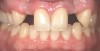

Fig 10. Case 2: Missing tooth No. 7 was extracted 3 months before implant placement.

Figure 10